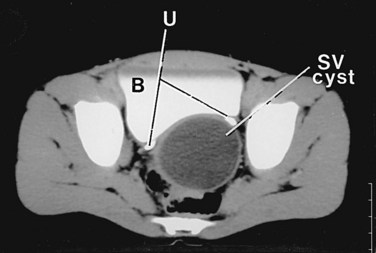

Computed tomography (CT) has also been used to evaluate the seminal vesicles. The normal appearance of the seminal vesicles on CT is that of paired structures just below the bladder with medium contrast similar to muscle (Goldstein and Schlossberg, 1988). A seminal vesicle cyst imaged by CT scan appears as a well-defined retrovesicular fluid density with the attenuation of water, from 0 to 10 Hounsfield units, cephalad to the prostate gland (Fig. 37–19). CT accurately images seminal vesicle anomalies, and is a good modality to allow for imaging of the ipsilateral kidney concomitantly (Arora et al, 2007).

Seminal vesicle cysts are thought to be secondary to ejaculatory duct obstruction and can be congenital or acquired (Heaney et al, 1987; King et al, 1991; Conn et al, 1992). Seminal vesicle cysts are associated with ipsilateral renal agenesis or dysplasia in two thirds of patients; the cysts are secondary to maldevelopment of the distal mesonephric duct and are an error in ureteral budding (Beeby, 1974). Seminal vesicle cysts have also been associated with polycystic kidney disease. In one report, seminal vesicle cysts were identified in 60% of patients with polycystic kidney disease, and some authors recommend that all patients with seminal vesicle cysts undergo renal imaging (Alpern et al, 1991; Hihara et al, 1993; Danaci et al, 1998). Seminal vesicle cysts should only be treated if they are symptomatic or result in ejaculatory duct obstruction and affect fertility (Surya et al, 1988).